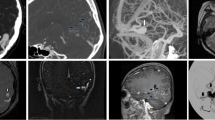

According to intraoperative findings, 40% (10/25) of the aneurysms were intracavernous, 8% (2/25) transitional and 52% (13/25) intradural, whereas MRI scans indicated 44.4% (11/25) of the aneurysms as intracavernous, 4% (1/25) as transitional and 52% (13/25) as intradural (Tables 1 and 3). Examples of intracavernous, transitional and intradural aneurysms are presented in Figs. 1, 2, 3, 4. Figure 5 presents a transitional aneurysm previously classified as intracavernous on MRI.

Coronal T2-weighted magnetic resonance imaging (MRI) scans acquired with a 3D fast spin-echo sequence showing anterior to posterior views of the anatomoradiological markers of the paraclinoid region with the reflection of the dura-mater represented by the yellow line. The anterior clinoid process and optic pillar are identified in green (panels A–I), the optic nerve in gold, the anterior curve of the internal carotid artery (ICA) in red (panels C–H), the horizontal segment of the cavernous ICA (panel I) and the aneurysm itself by red arrows (panels E–I). Note that the posterior portion of the transitional aneurysm projects into the subarachnoid space — located above the distal dural ring (interrupted yellow line)

Coronal T2-weighted magnetic resonance imaging (MRI) scans acquired with a 3D fast spin-echo sequence showing anterior to posterior views of the anatomoradiological markers of the paraclinoid region as in Fig. 1 except that the markers are not highlighted (panels A–D). The transitional aneurysm is indicated by white arrow heads (panels E–I). Note that the posterior portion of the transitional aneurysm (black arrow) projects into the subarachnoid space

Cerebral digital subtraction angiography (DSA) of intradural aneurysm #22 (see Table 1) showing anteroposterior (panel A) and profile (panel B) views. Note the medial and inferior projection of the aneurysm (white arrows). Coronal T2-weighted magnetic resonance imaging (MRI) scans with a 3D fast spin-echo sequence showing anterior to posterior views of the anatomoradiological markers of the paraclinoid region and intradural aneurysm #22 (panels C–F). Note the hyper-intense signal from the cerebrospinal fluid (white arrows). In panel G–I, three-dimensional time-of-flight (TOF) magnetic resonance angiography was employed to enhance the view of the aneurysm (white arrows)

Cerebral digital subtraction angiography (DSA) of intracavernous aneurysm #19 (see Table 1) showing anteroposterior (panels A and C) and profile (panels B and D) views. Note the medial projection of the aneurysm (white arrows). Coronal T2-weighted magnetic resonance imaging (MRI) scans with a 3D fast spin-echo sequence showing anterior to posterior views of the anatomoradiological markers of the paraclinoid region and intracavernous aneurysm #19 (panels E–H). Note the hyper-intense signal from the cerebrospinal fluid around the distal dural ring and no contact between CSF and the aneurysm (arrow heads)

Cerebral digital subtraction angiography (DSA) of aneurysm #5 that caused intertechnique disagreement (see Table 1) showing anteroposterior (panel A) and profile (panel B) views. Note the medial projection of the aneurysm (white arrows). The relationship between the aneurysm and bony structures are shown (panels C and D). Coronal T2-weighted magnetic resonance imaging (MRI) scans with a 3D fast spin-echo sequence showing anterior to posterior views of the anatomoradiological markers of the paraclinoid region and the intracavernous (MRI)/transitional (M) aneurysm #5 (panels G–J; aneurysm — white arrows)